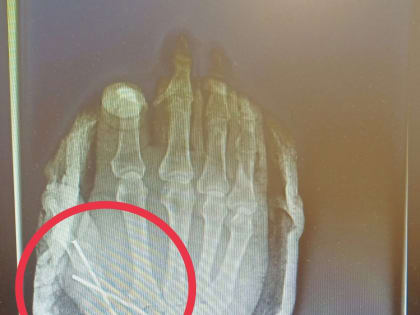

В Татарстане врачи спасли от ампутации палец 54-летнего мужчины, отрезанный болгаркой

Врачи Нижнекамской центральной районной многопрофильной больницы рассказали о спасении 54-летнего пациента, который работая на даче случайно травмировался болгаркой.

Опасный инструмент: врачи спасли дачнику палец, отрезанный болгаркой

В Татарстане врачи спасли мужчине палец на руке – был риск его полной ампутации.